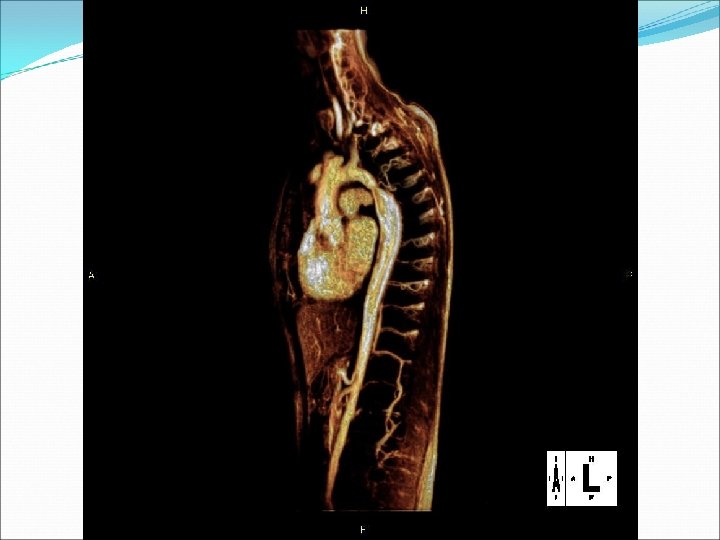

Koarktace aorty: diagnostika �CT nebo magnetická rezonance metodou volby: zobrazí i odstupy velkých tepen, kolaterály, aneuryzmata �Echokardiografie �Srdeční katetrizace: tlakový rozdíl mezi oblastí nad místem koarktace a oblastí pod ní �Aortografie �Skiagram hrudníku: „znamení trojky“, uzurace dolního okraje žeber při dilataci interkostálních tepen �EKG obraz hypertrofie levé komory.

�Obrázky str 126, 127